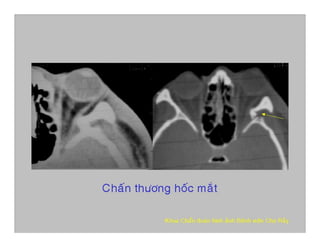

Nam, 25t, mù mắt (T), CTSN

Vỡ xương trán, thành trong hốc mắt, lỗ thị giác (Bỏ sót CT thường qui)